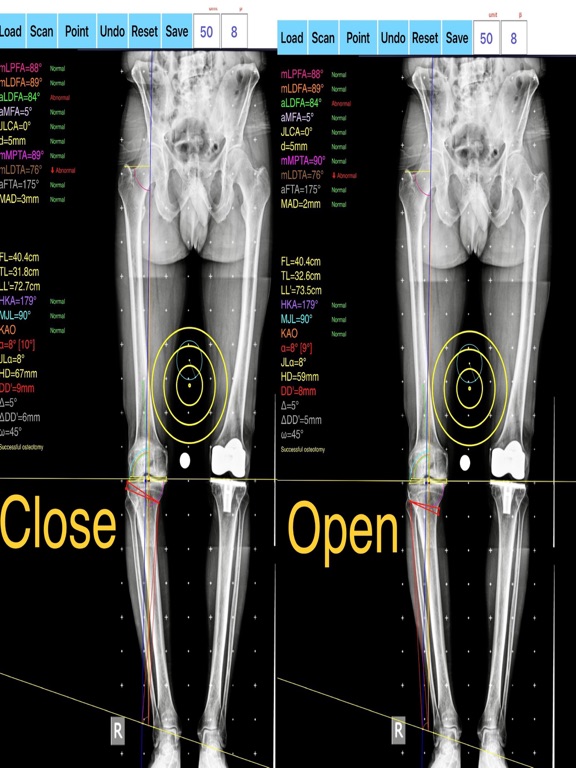

-the amount of correction preoperatively by calculating the dimension of  wedge size , the correction angle and osteotomy gap opening or closing.

-mechanical axis deviation (in mm) MAD, anatomical and mechanical femoral axes angle (aMFA),mechanical lateral proximal femoral angle (mLPFA), mechanical lateral distal femoral angle(mLDFA), joint line convergence angle (JLCA),mechanical medial proximal tibial angle (mMPTA), Mechanical lateral distal tibial angle (mLDTA), Hip Knee Ankle line (HKA) ,Mid joint line (MJL) orientation.

-objectively the deviation or deformity in the frontal plane (varus or valgus) and differentiate the level of deformity (femoral and or tibial origin) and according to measured angles objectively suggest where indicated, medial or lateral, open or closed-wedge distal femur osteotomy or high-tibial osteotomy or double osteotomies  and avoiding unwanted obliquity of the joint line

-evaluate in real time the success of intended osteotomy by evaluating the kinematic alignment of the knee (KAO), avoiding residual joint obliquity or malalignment.

-pressing + or - button, one degree of correction is added or subtracted respectively and the second plane of osteotomy emerges and printed in screen real offering real time simulation of the wedge osteotomy in an instant to comprehend in real time what parameters are affected and modify favourably the correction angle. All above mentioned angles and all limp axes are redrawn and updated accordingly for the given new correction angle. The drawn schematic gives the impression of settings  act as a whole interchangable interacting unit.

-to combine correction- Biplanar-, at coronal plane and  sagittal  plane (based on Hernigou 2001 calculations ) on tibia slope and provide the direction of the plane (ω angle) in which the osteotomy (open or closed) should be made ,the height the opening or closing wedge and the correction angle (Δ angle),

-to simulate, before real bone cuts are done and try different strategies in relation to the location, the type of osteotomy, the joint obliquity without to redraw in paper board countless drawings in an effort to achieve the optimal correction and mean while taking into account and balancing all influencing  preoperative factors.